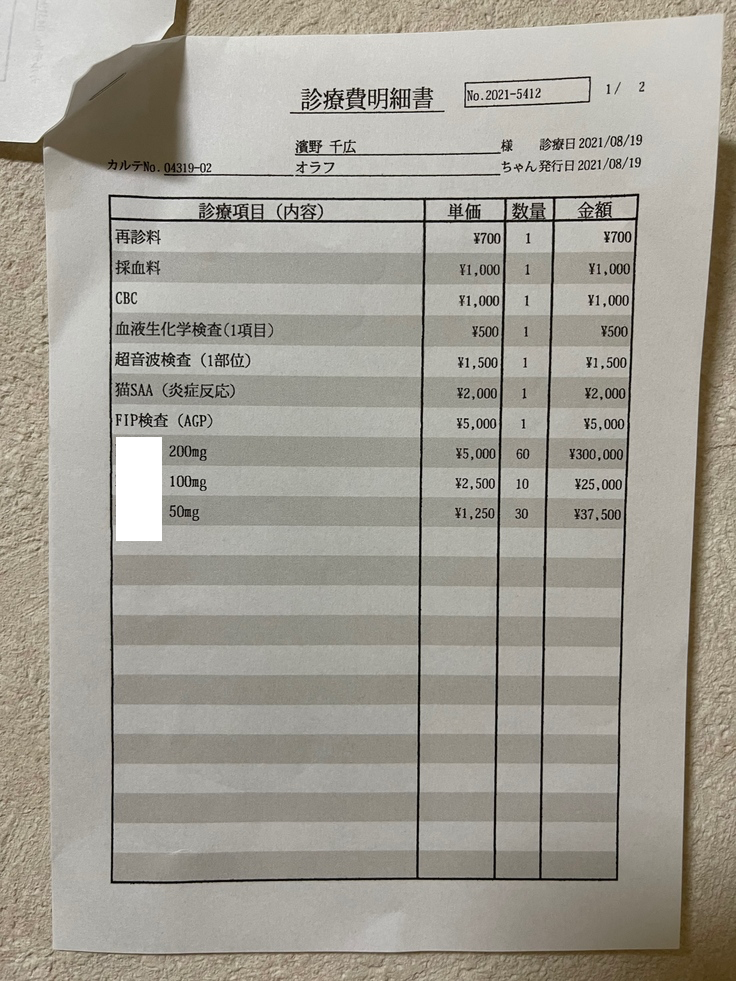

8月19日

定期検査(投薬を始めて2週間後)です。

4cm程あった肉芽腫が、1.2cmとすごく小さくなっていました。

大きかった肉芽腫がたった2週間でこんなに小さくなることに驚きました。

オラフの食欲も戻ってきて、だいぶ元気にもなってきました。

84日間新薬をのませて治してあげたいという気持ちがさらに強くなりました。

8月19日の肉芽腫 7月29日の肉芽腫

検査費と薬代です。